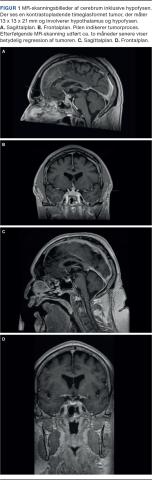

En 64-årig mand, der havde biopsiverificeret sarkoidose med moderate lungeforandringer samt ledaffektion og var velbehandlet på methotrexat gennem fire år, blev indlagt i en akutmodtagelse til udredning for træthed. Trætheden var progredieret over tre uger, og han beskrev det selv som udtalt fysisk og psykisk træthed. Han havde intermitterende frontalhovedpine, svimmelhed, sløret syn og påvirket kognition. Den objektive undersøgelse viste normale forhold uden neurologiske udfaldssymptomer, og initiale biokemiske undersøgelser forud for påbegyndelse af behandling viste let påvirkede inflammationsmarkører og stigende plasmaværdier af interleukin-2-receptor (IL-2R) og peptidyldipeptidase A (angiotensinkonverterende enzym, ACE) sammenholdt med tidligere målinger. Hypofyseprøver viste flg. værdier lavt P-thyrotropin med lav P-thyroxin og et spotkortisolniveau på < 14 nmol/l (referenceværdi: 171-536 nmol/l) og P-kortikotropin (adrenokortikotropt hormon, ACTH) 8 ng/l (referenceværdi: 7-64 ng/l) samt affektion af gonadeaksen (Tabel 1). CT af cerebrum viste ingen akutte forandringer, men diffus slimhindefortykkelse i bihulerne. Den modtagende læge konfererede med vagthavende reumatolog, og mistanken om neurosarkoidose blev bestyrket. Lumbalpunktur viste tegn på inflammation i cerebrospinalvæsken med et leukocytniveau på 20 x 106/l af mononukleær type, men normal koncentration af protein og glukose. I de supplerende undersøgelser af rygmarvsvæsken påvistes ingen infektion og malignitet. En MR-skanning af cerebrum inklusive hypofysen viste en kontrastopladende timeglasformet tumor, der målte 13 x 13 x 21 mm og involverede hypothalamus og hypofysen. Af radiologen blev den beskrevet som værende forenelig med hypotalamisk-hypofysær sarkoidose (Figur 1A + B). Der blev indledt behandling med methylprednisolon 500 mg x 1 dagl. i tre dage for neurosarkoidosen og for den akutte binyrebarkinsufficens. Få dage efter angav patienten at være i nærhabituel tilstand. En kontrolskanning efter to måneder viste total regression af tumorprocessen (Figur 1C). I efterforløbet blev der indledt substitutionsbehandling med hydrokortison og stofskiftehormon. To måneder efter symptomdebut udviklede patienten diabetes insipidus, hvorfor der blev iværksat vasopressinbehandling.